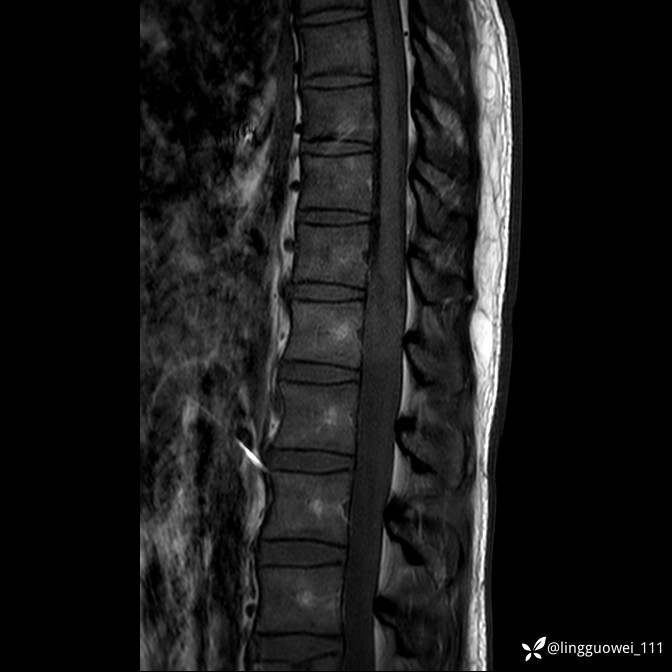

男,38岁,反复腰痛伴双腹股沟区痹痛半年,加重1月。

腰椎MR,注意脊髓异常信号,与伪影鉴别,一不小心就会漏诊

T2WI T2WI+FS

+C